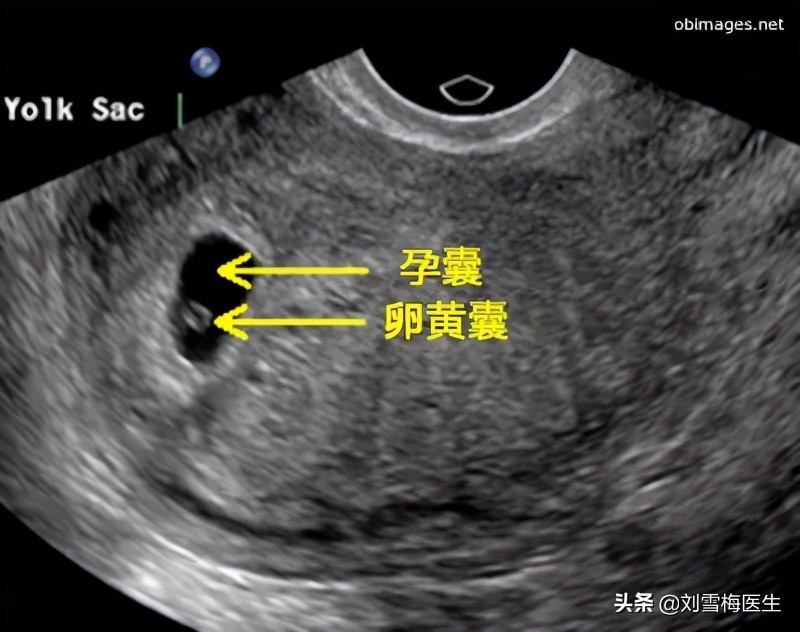

孕囊、胎芽、胎心,在孕早期是根据时间顺序出现的。也就是在子宫内先出现孕囊(确定宫内孕),再出现胎芽(确定孕周),最后出现胎心(提示宝宝存活)。

孕囊(孕30—40天)

是怀孕最初胚胎的形态,被羊膜、血管网包裹的小胚胎。

孕囊一般只能在孕早期看到。一般情况下,怀孕5周以后,B超可看见小胎囊,胎囊约占宫腔不到1/4,或可见胎芽。在孕11周时,通过B超就可以看到孕囊完全消失,胎盘清晰可见,而孕囊担当的就是一个护宝使者的使命。

孕囊位置在子宫的宫底、前壁、后壁、上部、中部都属正常;形态圆形、椭圆形、清晰为正常;